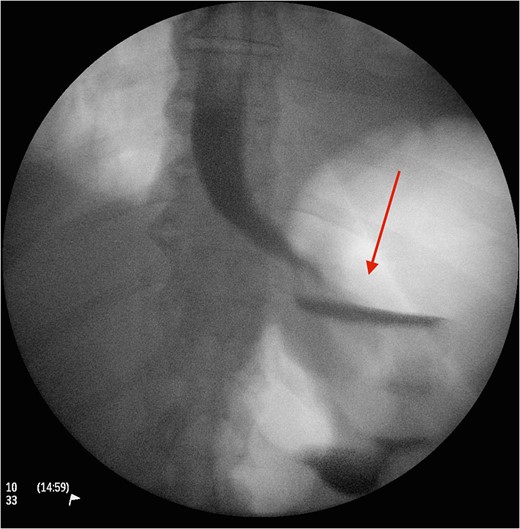

Cross section CT image demonstration the site of the band with no collection (red arrow).

The gold standard investigative modality is endoscopy [5]. CT is another option, although such tool is more useful in detection of associated complications such as extend, site and type of perforation and/or contaminations. Upon detection of erosion, removal remains the only option and should be performed promptly to avoid associated mortality and morbidity. The use of prophylactic antibiotics in such circumstance is not clear but in our centre we highly recommend their use upon suspicion of diagnosis. In case of band migration and/or erosion, endoscopic removal has shown promising results, although such technique is not always applicable and their open retrieval has been suggested and performed. Another option is standard laparoscopic division and retrieval. Although feasible and successful, this method does not always permit a comprehensive visualization, dissection and division. In our reported case, we encountered the aforementioned factors. Therefore, the decision was made to create anterior gastrotomies (extension of the port to stomach) to facilitate full division, retrieval of the gastric band and assessment of the erosion and its repair if necessary through transgastric approach. The authors believe, such procedure is safe and feasible in circumstances when standard laparoscopic retrieval is not possible. Placement of a new gastric band is usually delayed for a period of 3 months in such cases [3, 5]. In the reported case, patient made an uneventful recovery and was discharged 3 days following the procedure.